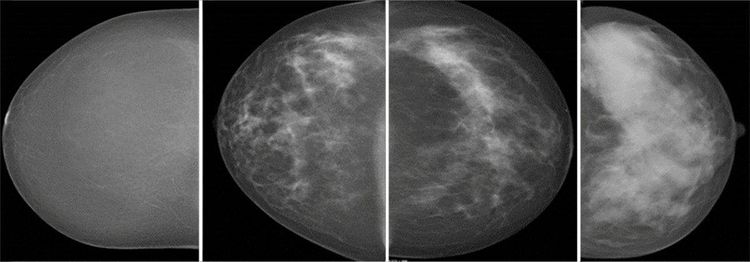

Researchers using automated breast density measurements have found that women with mammographically dense breast tissue have higher recall and biopsy rates and increased odds of screen-detected and interval breast cancer.

This is partly because the superimposition of dense breast tissue on mammograms leads to a masking effect, causing some cancers to go undetected.

But the majority of those studies relied on subjective density assessments – most commonly, the radiologist’s subjective interpretation using the American College of Radiology’s Breast Imaging Reporting and Data System (BI-RADS).

The automated software classified breasts as dense in 28 per cent of the screening examinations.